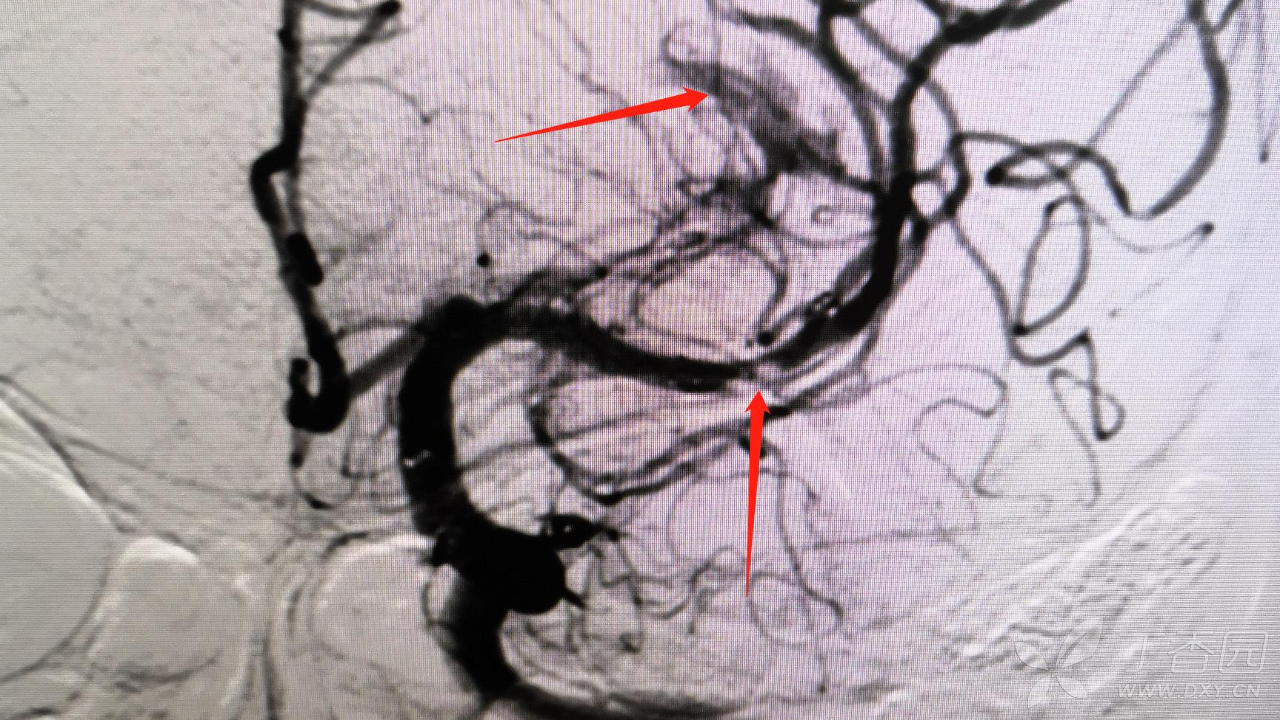

简述手术过程:采用同轴技术将8FGuiding置于左侧颈内动脉颈段,造影显示左侧大脑中动脉M2段局部白色血栓样病变,微导丝及微导管导引下将6F中间导管置于左侧大脑中接近白色血栓样病变,经中间导管尾端负压抽吸未见回血,持续负压吸引下将中间导管回撤至颈内动脉末端后,回抽未见血栓,再次造影显示左侧大脑中动脉完全闭塞,主手术者考虑血管内膜受损所致夹层闭塞。更换微导丝配合微导管通过闭塞段,将微导管置于闭塞远端,撤出微导丝,经微导管造影确认真腔,交换长导丝将1.5mm-15mm球囊置于狭窄段(局部白色血栓样病变段),给予8ATM扩张,造影见局部白色血栓样病变段90%狭窄,远端血流恢复,经导管给予欣维宁10ml,观察15min,再次造影见残余狭窄仍有90%,贴覆3.0mm-15mm支架于狭窄段,再次造影见残余狭窄约80%,支架覆盖部位造影显示仍有白色类似血栓样病变。由于多次使用及更换微导丝探测,微导丝进入左侧大脑中远端分支,远端分支血管周围可见造影剂外渗,未来得及中和肝素,患者呕吐咖啡色样胃内容物,血氧饱和度下降,心率增快,生命体征不平稳,向家属告知手术结果后终止手术。

询问另一位临床经验丰富神经介入二线医师:左侧大脑中动脉M2段局部白色血栓样病变考虑血栓。但是询问负责该患者主管手术二线考虑夹层样次全闭塞。

疑问:1.如果是血栓,为何抽吸导管接近抽吸后未见血栓?

2.为何中间导管抽吸后再次造影显示左侧大脑中动脉完全闭塞?

3.球囊扩张后再次造影显示左侧大脑中远端血流恢复?

4.如果是夹层样病变,为何球扩及支架置入后局部白色血栓样病变一直存在?

5.影像学(DSA)如何鉴别血栓、夹层及粥样硬化斑块,有无特征性影像学表现?